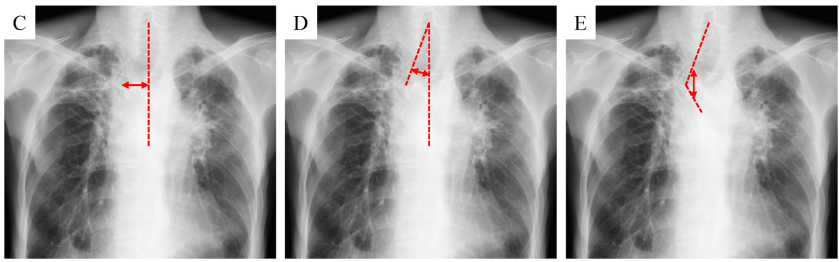

論文Fig.1(胸部X線で測る3指標)を、文章で整理するとこうです。

- 偏位距離:正中線から最大偏位点までの距離(C)

- 偏位角:正中線と「輪状軟骨中心→最大偏位点」を結ぶ線の角度(D)

- 屈曲角:輪状軟骨中心→最大偏位点→気管分岐部、の折れ曲がり角度(E)